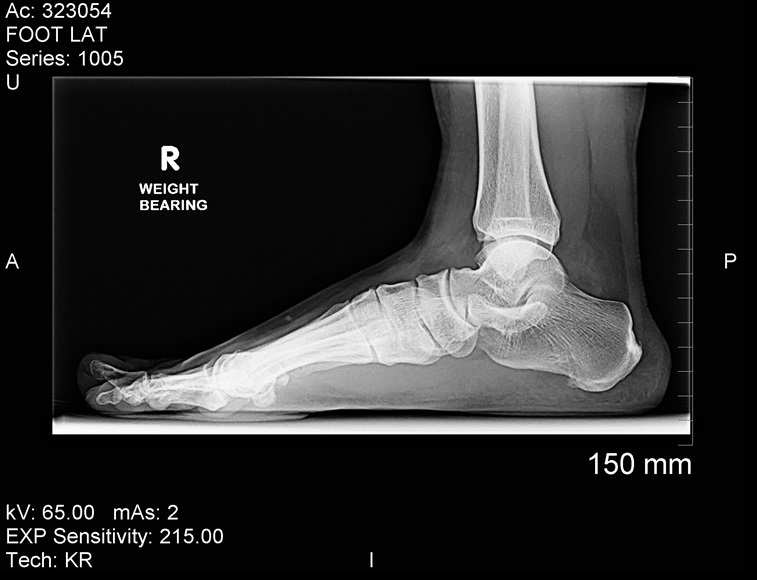

Calcaneal Bone Pain - Calcaneal Spurs: Bone spurs, also known as osteophytes, are bony projections that form along joints. Bone spurs form due to the increase in a damaged joint's surface area. This is most commonly from the onset of arthritis. Bone spurs usually limit joint movement and typically cause pain.